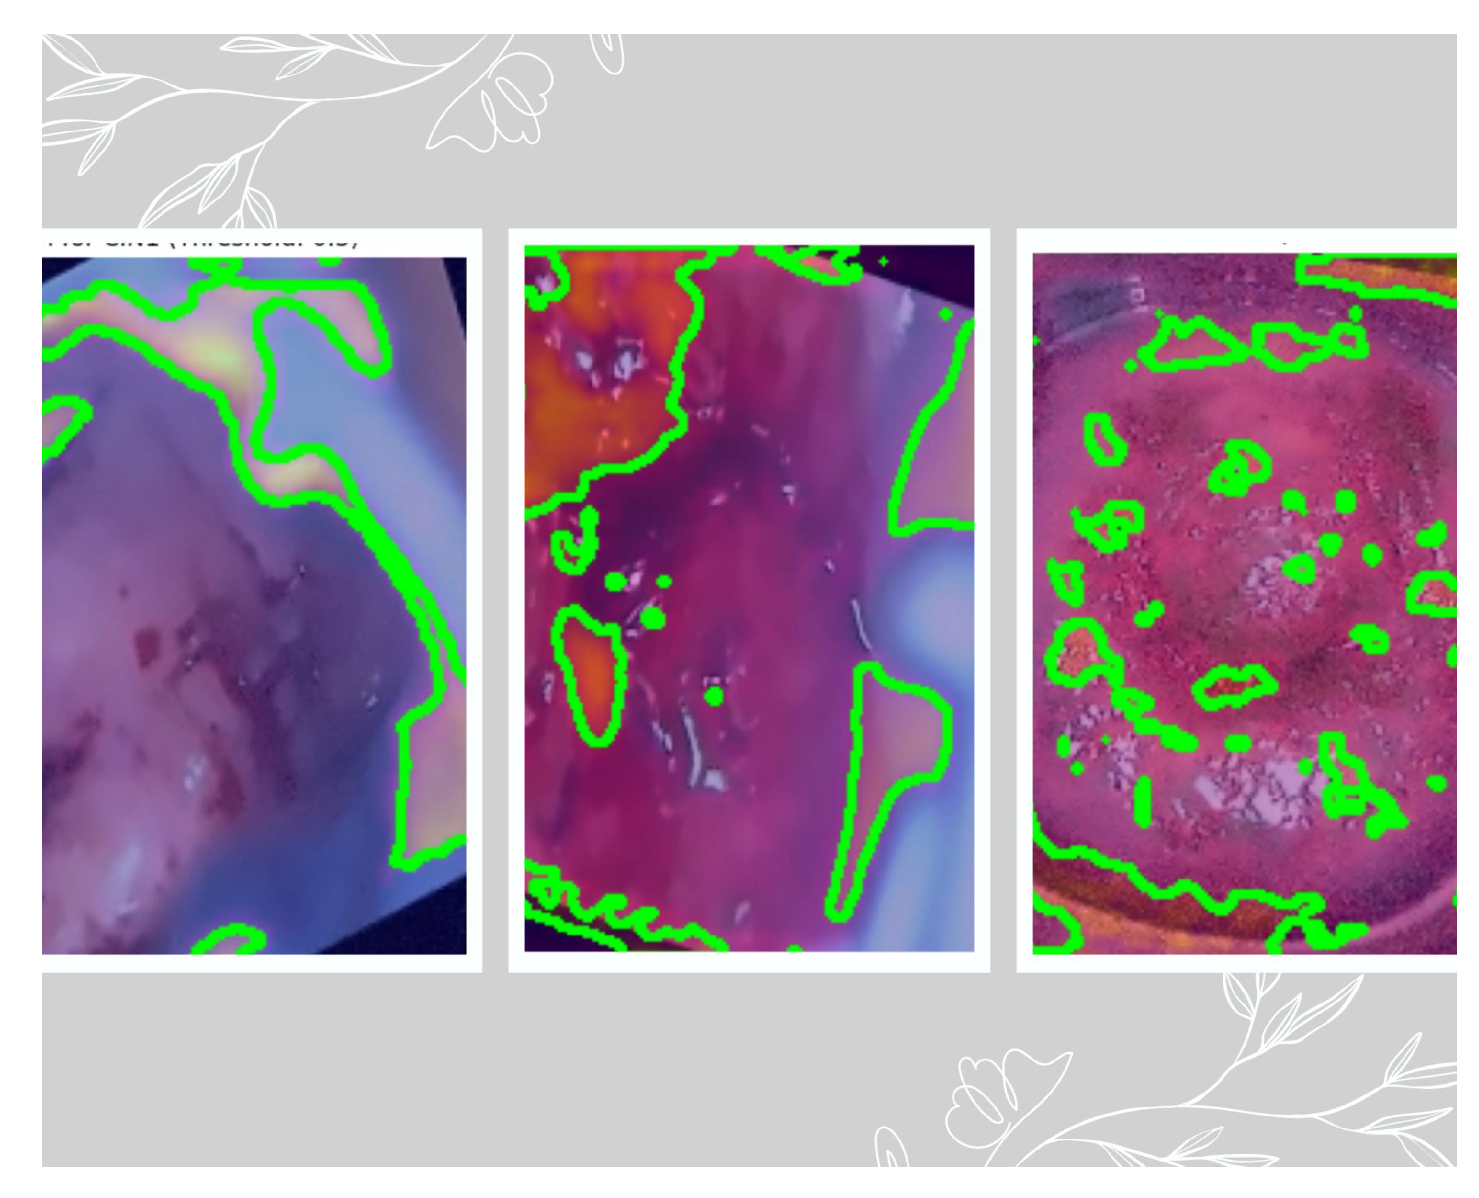

Purpose: Grad-CAM is used to interpret which parts of an input image are most important for a model’s prediction. In our case, Grad-CAM is applied to convolutional layer 5 (which captures high-level patterns) and combined with the gradients of the predicted class. The resulting heatmap overlays on the original colposcopy image, highlighting areas that influenced the model’s decision based on three different thresholds: 0.3, 0.5, and 0.6. These thresholds are empirically selected starting with common values like 0.3, selecting a midvalue of 0.5 and a little higher value of 0.6. Since the final validation accuracy is not very high, we fine-tuned these thresholds to generate a binary mask and to mark the ROI. This ROI is also confirmed by the medical practitioner. Equation 4 and equation 5 provides the mathematical basis.

This section provides the result of PCA, which was used to reduce the vector size from 4096 to 3, as seen in Figure 9. Grad-Cam was associated in the deepest layer (5th convolutional layer). We have used three thresholds to decide on the best feature extracted. As per the suggestion of the medical practitioner, we have selected the images based on threshold 0.3 as the best feature extractor for the three classes. Figure 10 depicts the mask with the ROI for the three classes based on the 0.3 threshold, where the first image is of CIN1, the second image is of CIN2, and the third image is of CIN3. Figure 11 shows the ROC-AUC curve of the three classes, and finally Figure 12 is the confusion matrix for the three classes on the validation dataset of 600 images.